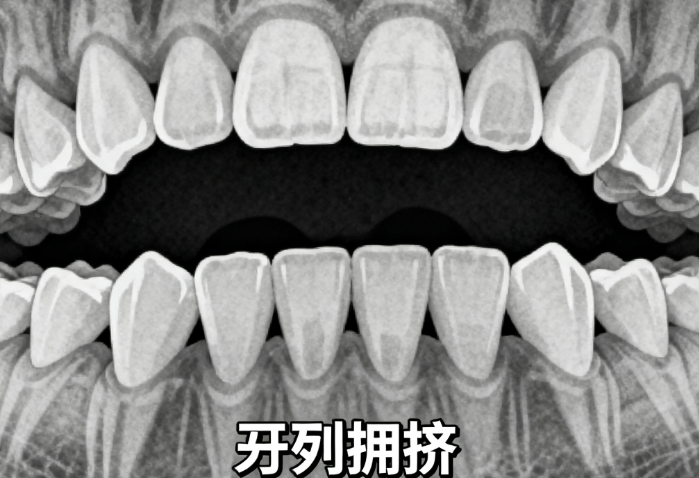

常州儿童牙齿矫正价格从2980元到45800元不等,差别挺大。影响价格的因素有矫正类型、医院等级、孩子年龄和牙齿问题等。比如MRC肌功能矫正器大概在2368到9800元,适合早期干预。而像隐